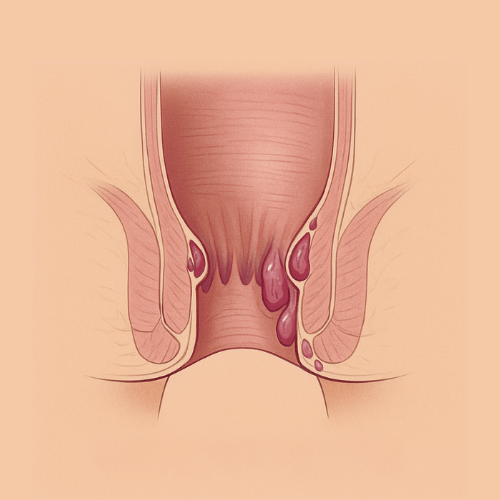

EMUAID is designed to relieve symptoms from over 100 difficult-to-treat conditions like eczema, psoriasis, nail fungus, hemorrhoids, shingles, acne, rashes, burns, cellulitis, and more. If it's red, itchy, cracked, painful, or inflamed- EMUAID may help.